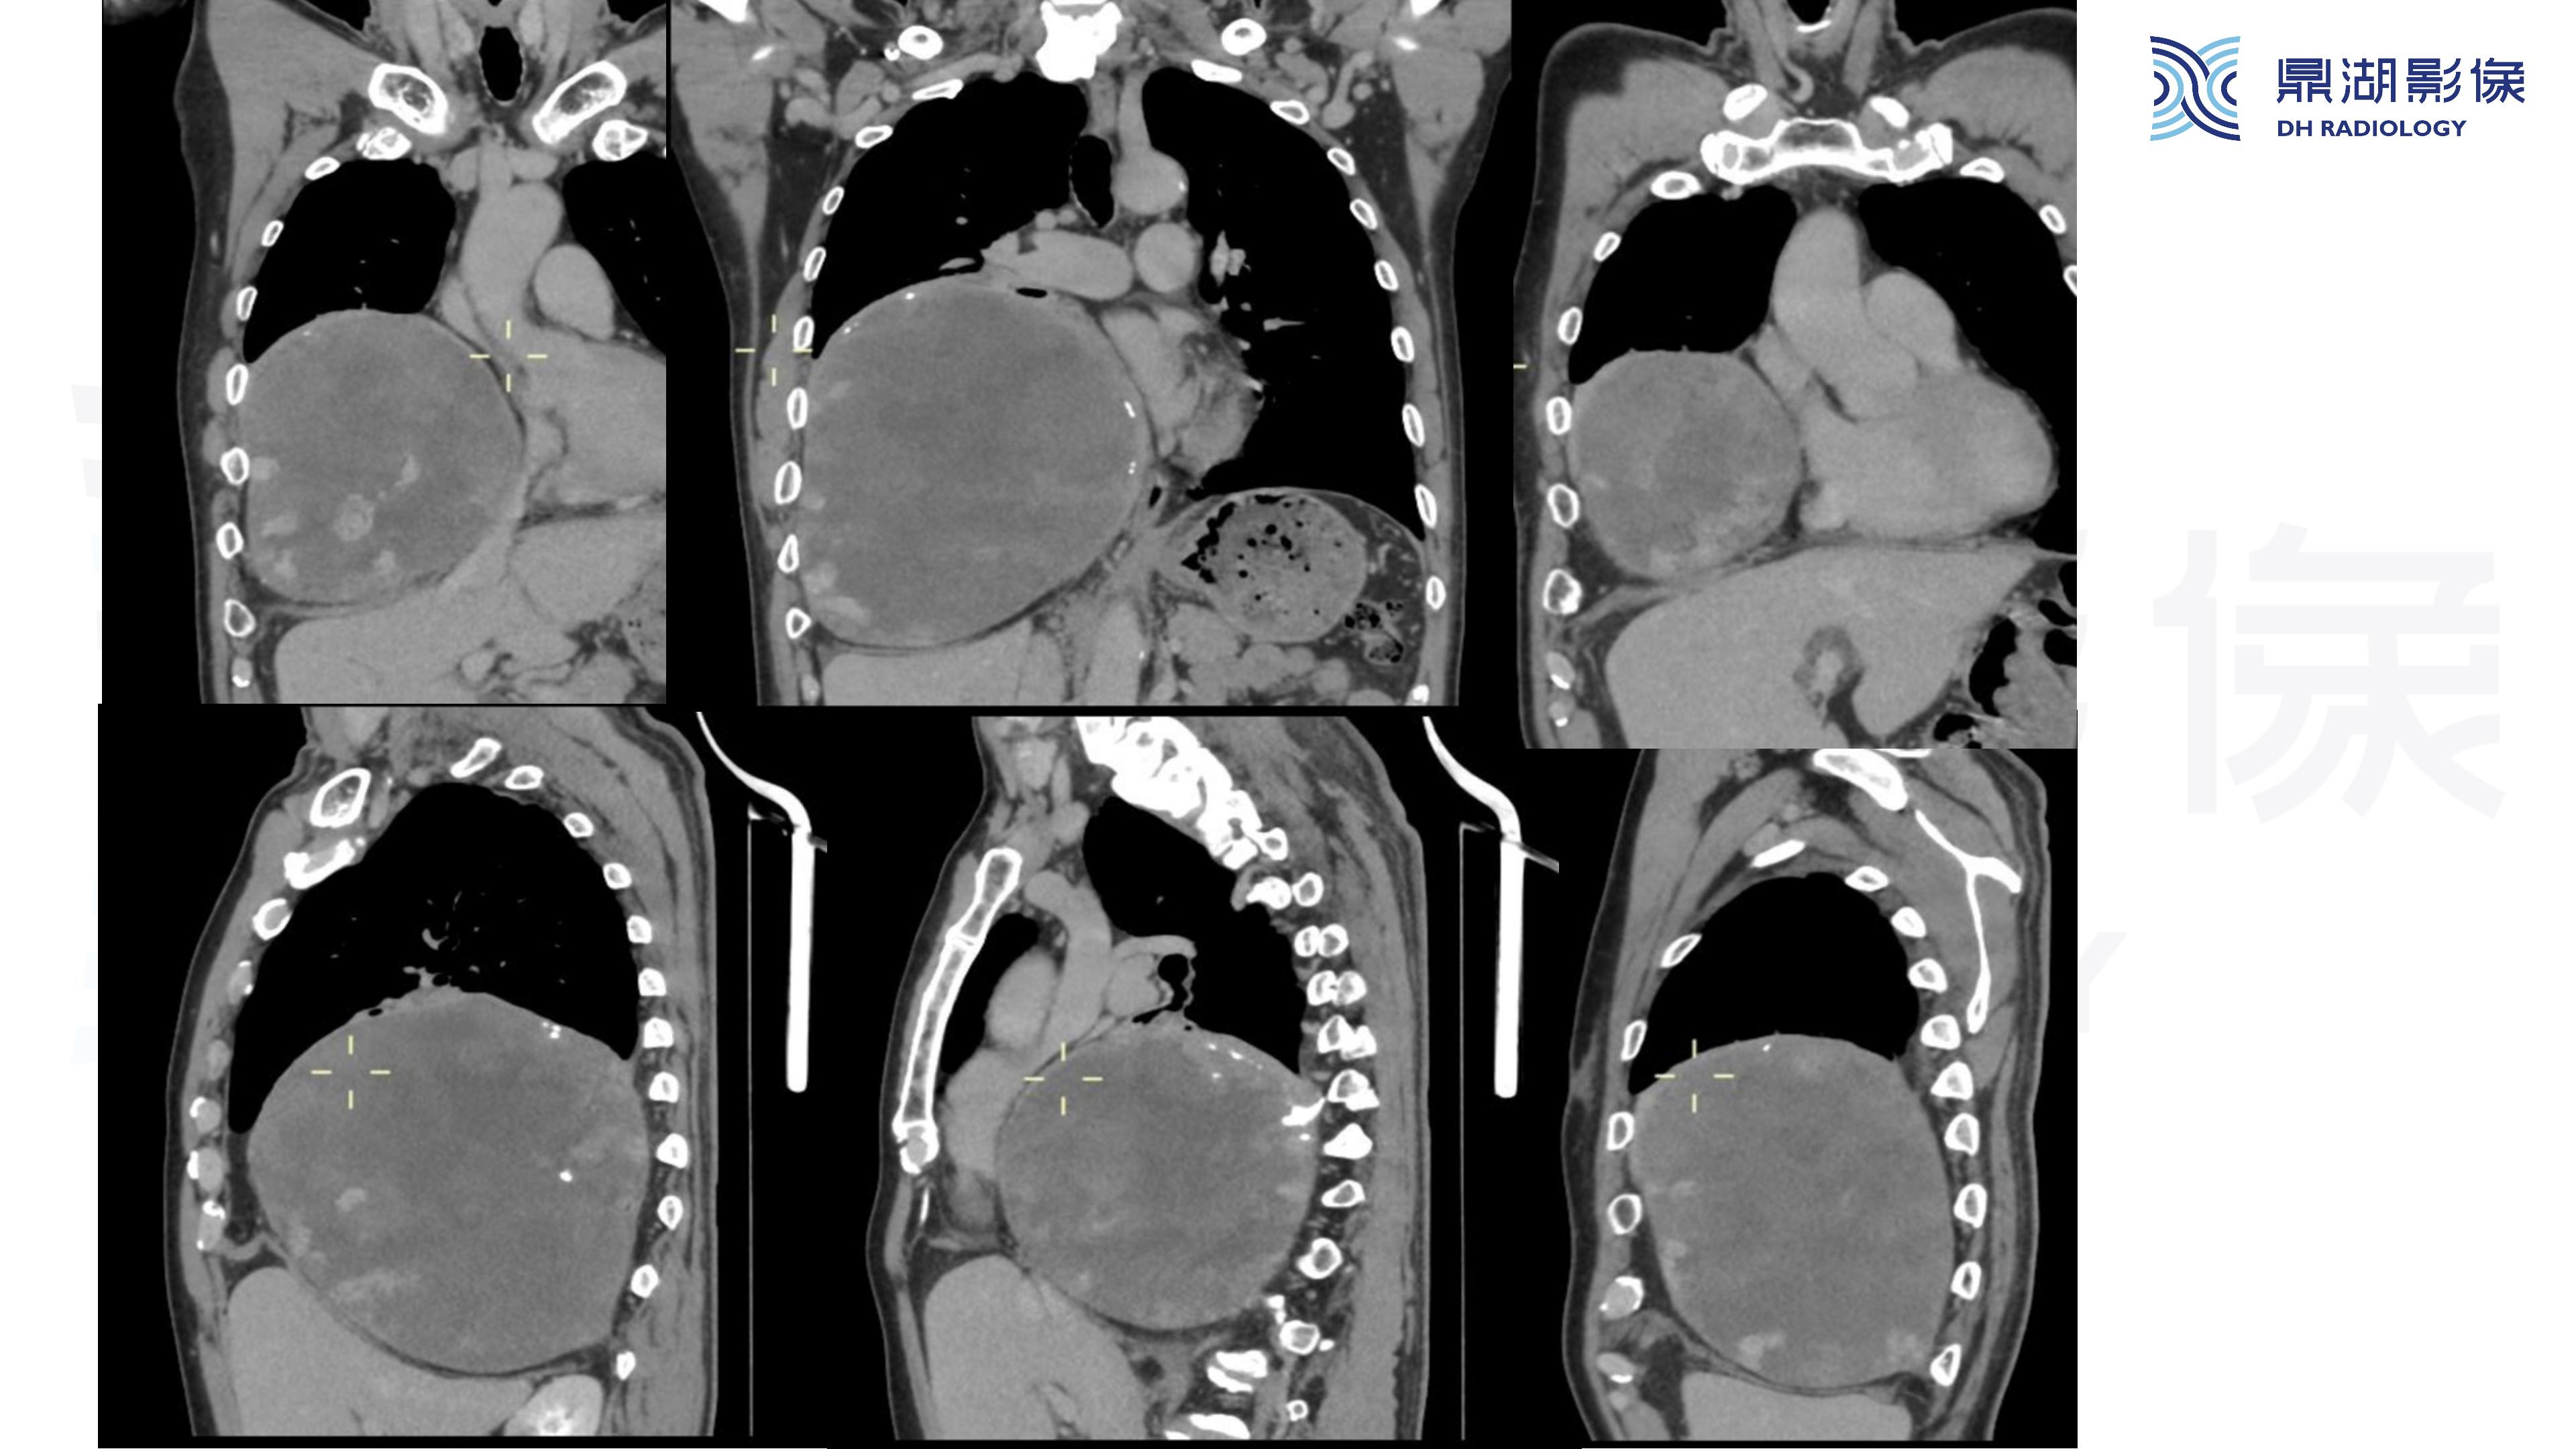

纵隔血管瘤-鼎湖社群读片病例